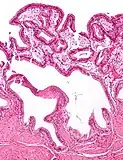

Cholesterolosis of gallbladder

Other names: Strawberry gallbladder, gallbladder cholesterolosis

Cholesterolosis of the gallbladder, also known as strawberry gallbladder, is a change in the gallbladder wall due to excess cholesterol.[1]

The name strawberry gallbladder comes from the typically stippled appearance of the mucosal surface on gross examination, which resembles a strawberry. Cholesterolosis results from abnormal deposits of cholesterol esters in macrophages within the lamina propria (foam cells) and in mucosal epithelium. The gallbladder may be affected in a patchy localized form or in a diffuse form. The diffuse form macroscopically appears as a bright red mucosa with yellow mottling (due to lipid), hence the term strawberry gallbladder. It is not tied to cholelithiasis (gallstones) or cholecystitis (inflammation of the gallbladder).[2]